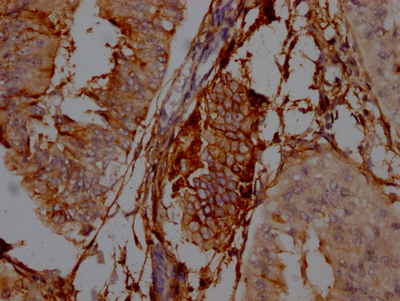

IHC image of CSB-RA978310A0HU diluted at 1:100 and staining in paraffin-embedded human colon cancer performed on a Leica BondTM system. After dewaxing and hydration, antigen retrieval was mediated by high pressure in a citrate buffer (pH 6.0). Section was blocked with 10% normal goat serum 30min at RT. Then primary antibody (1% BSA) was incubated at 4℃ overnight. The primary is detected by a Goat anti-rabbit IgG polymer labeled by HRP and visualized using 0.05% DAB.